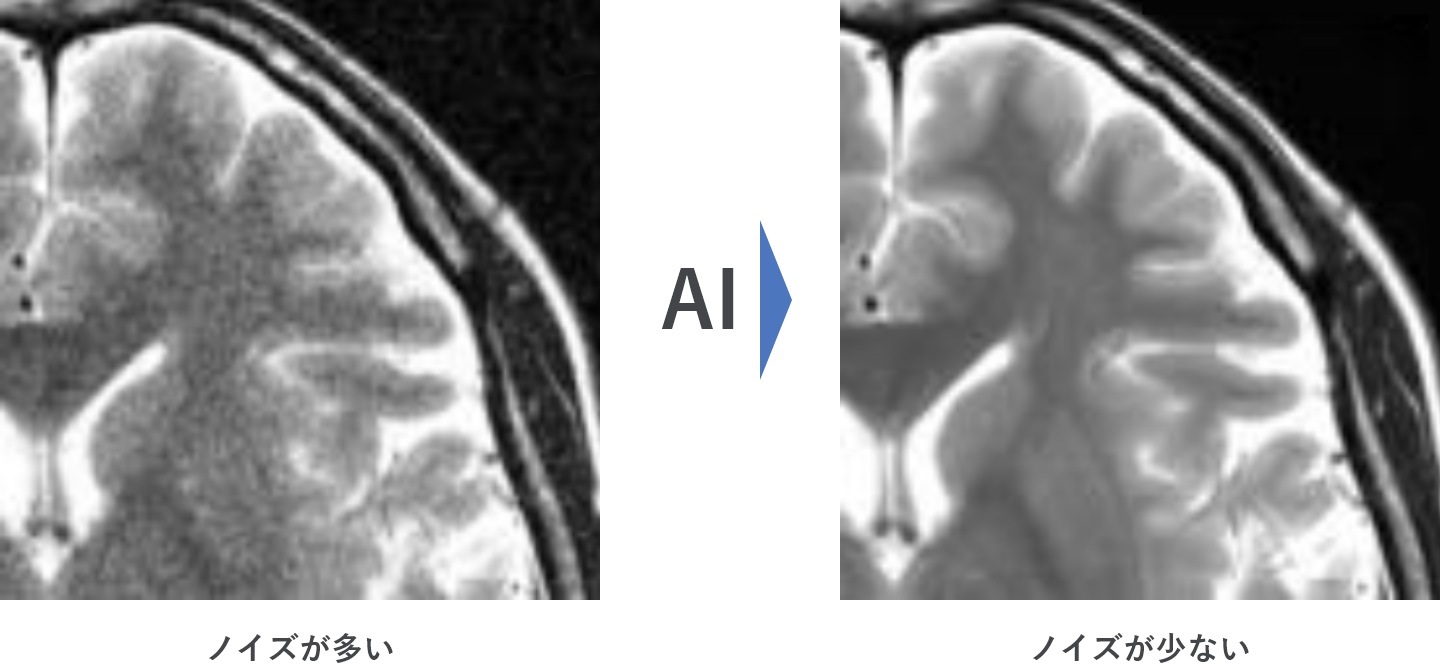

~最新のAI技術により「短い検査時間」または「3T相当の高画質」を実現します~

最新のAI技術であるディープラーニングを応用したノイズ除去技術を搭載しています。

3T相当のノイズの少ない画像を実現。また従来の1.5T装置と比較しても分解能を向上させることが可能です。